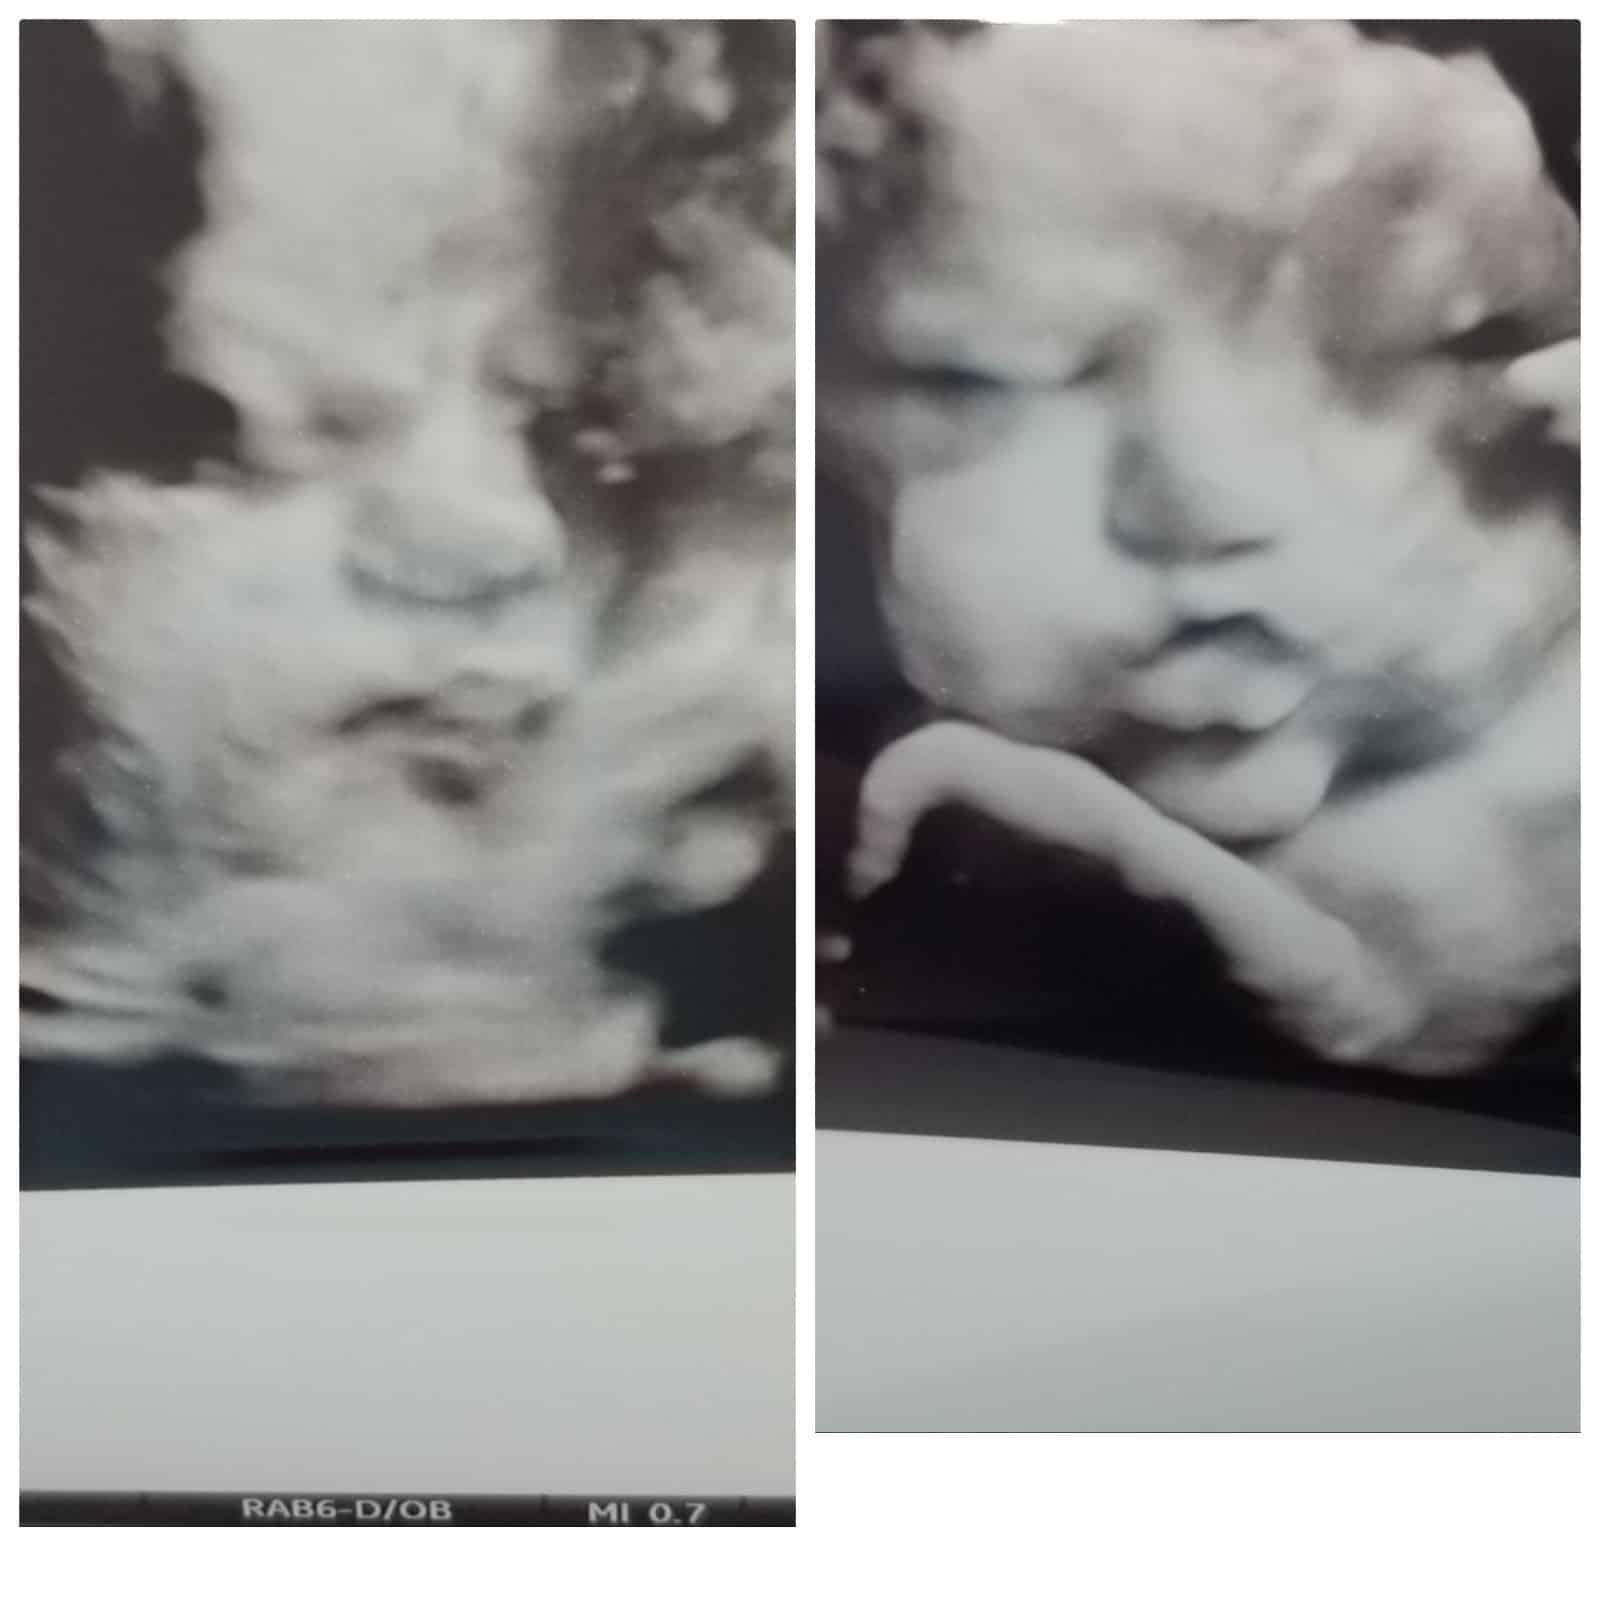

Ultrasound Photos at 34 Weeks Pregnant With Twins